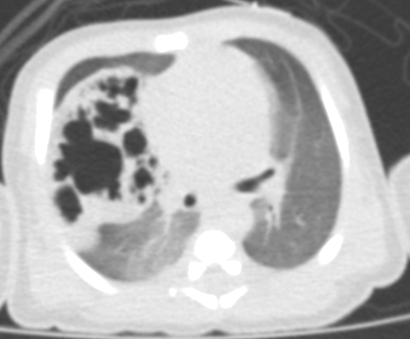

Figura 3. Ricostruzione TC: l'albero bronchiale con la lesione adenoido-cistica, evidenziata dopo sottrazione del parenchima polmonare circostante.